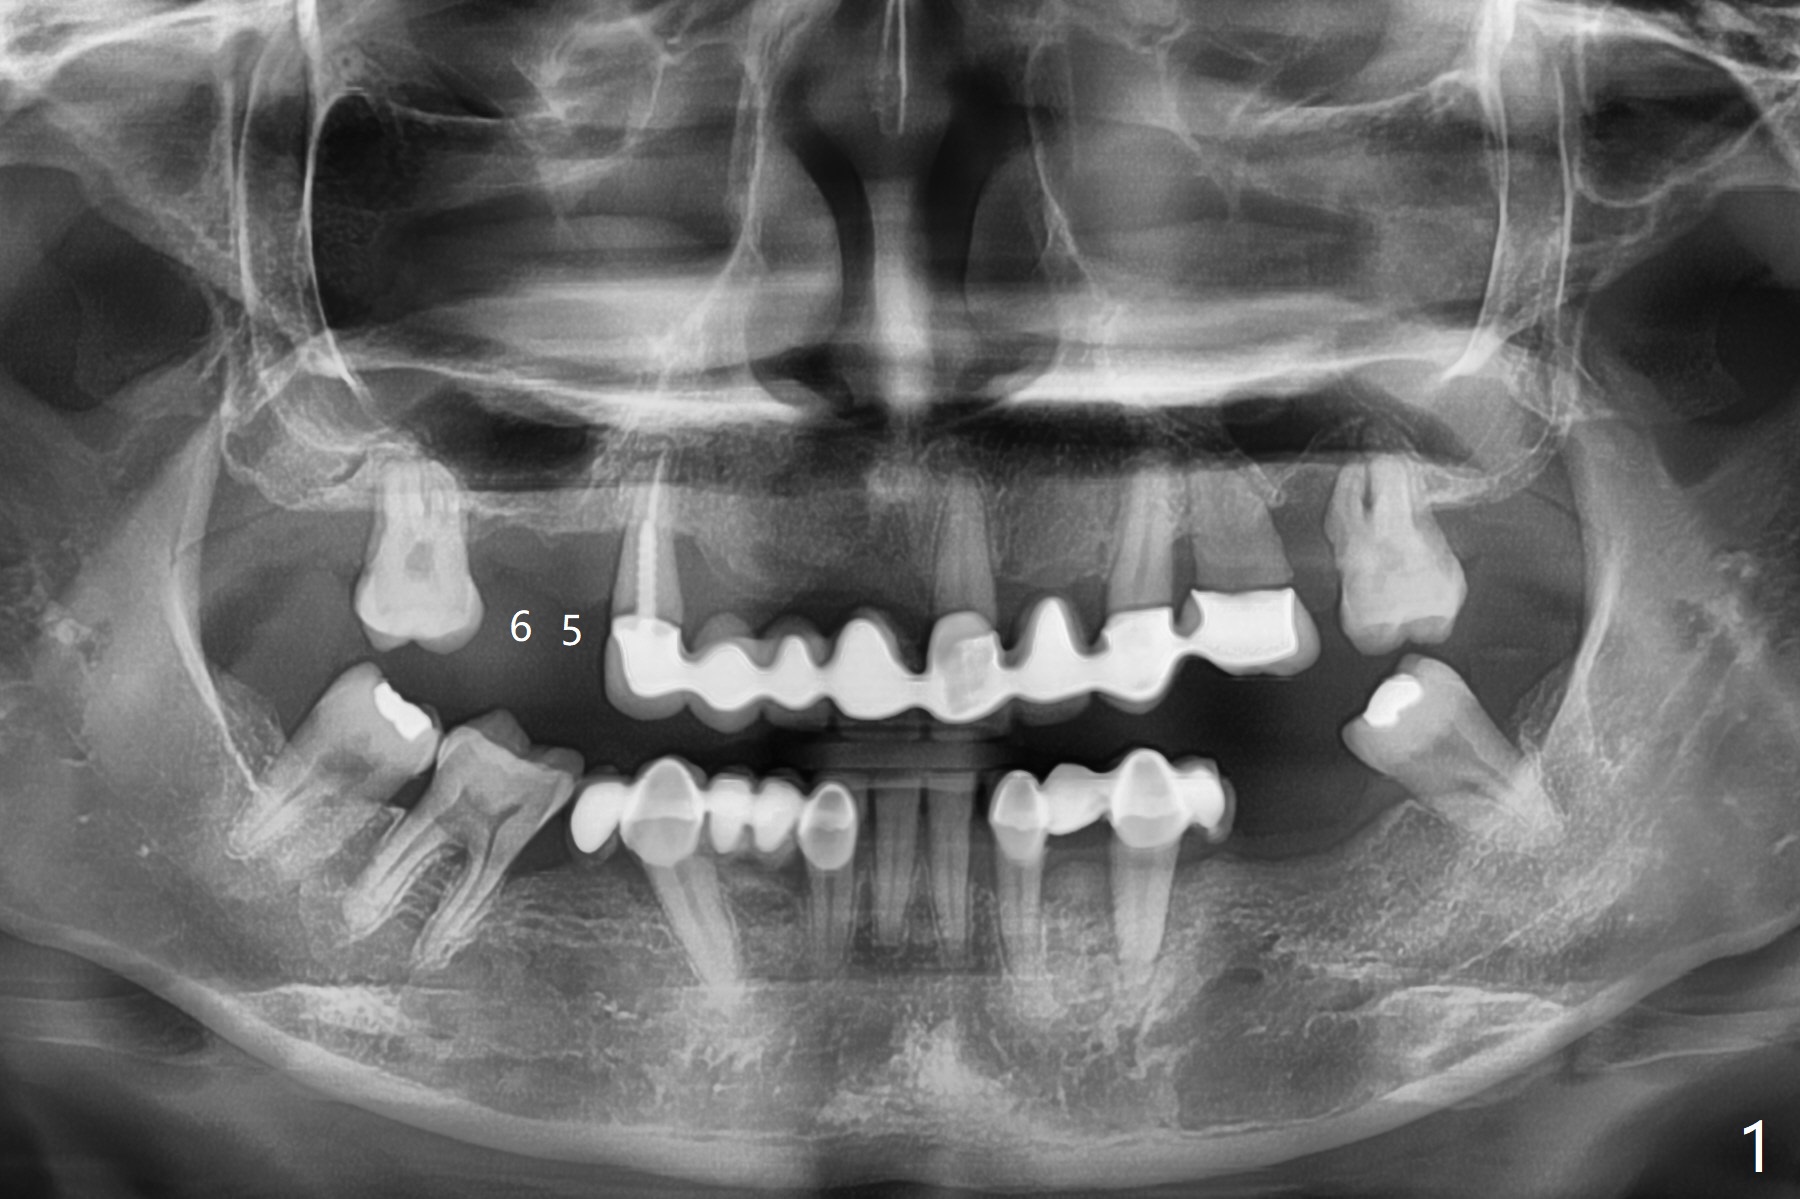

第一磨牙即种

不做第一磨牙即种后果预防第二种医源性疾病: 1毫米上颌骨